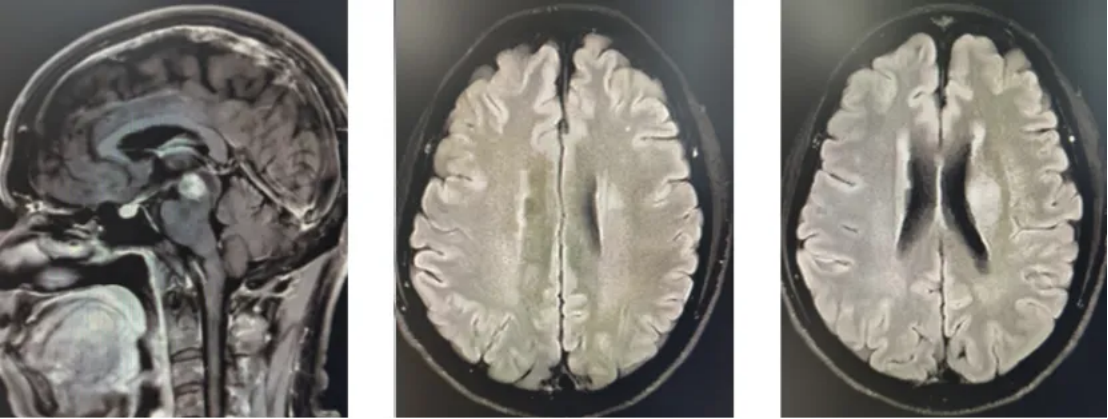

患者男性,61岁,主诉为“左眼视物模糊,左眼睑下垂和左眼球固定2月”,无头晕、头痛和肢体乏力等不适。2023-04-20在当地医院行MR检查,显示中脑、丘脑、基底节、放射冠、海马及颞叶深部多发异常信号,考虑肿瘤性病变,低级别胶质瘤可能(图1)。2023-04-25在我院行PET/MR检查,提示左侧脑室旁、左侧中脑、丘脑、颞叶海马区多发异常信号灶代谢略活跃,增强扫描中脑病灶明显不均匀强化,余病灶强化不明显,不除外恶性病变可能。2023-05-10在外院行立体定向中脑病变活检术,术后病理提示:病变组织符合DMG,免疫组化显示:IDH-1(散在弱+),Ki-67(约40%),MGMT(-),H3K27M(部分弱+,突变型)。最后诊断:DMG,H3K27M突变型,WHO 4级。

图1 初诊影像学